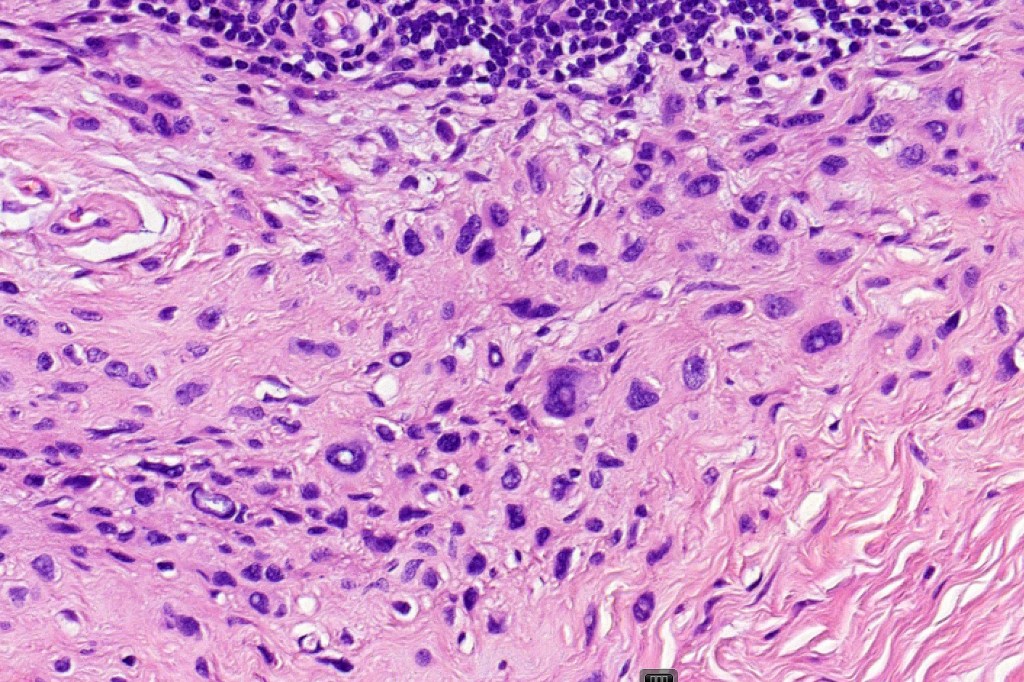

This is a rare variant of melanocytic nevus, so-named because it shares some of the features of ancient schwannoma and not because of its age! It most often arises on the face of older patients as a flesh colored or erthematous nodule. Its importance is that it may be mistaken as melanoma by the unwary.

Histological features

•Mixed cell population- pleomorphic cells (nevoid or Spitzoid)with vesicular or more often intensely hyperchromatic nuclei & often prominent nucleoli, admixed with banal nevus cells, intranuclear cytoplasmic pseudo-inclusions

•Very occasional mitoses may be found